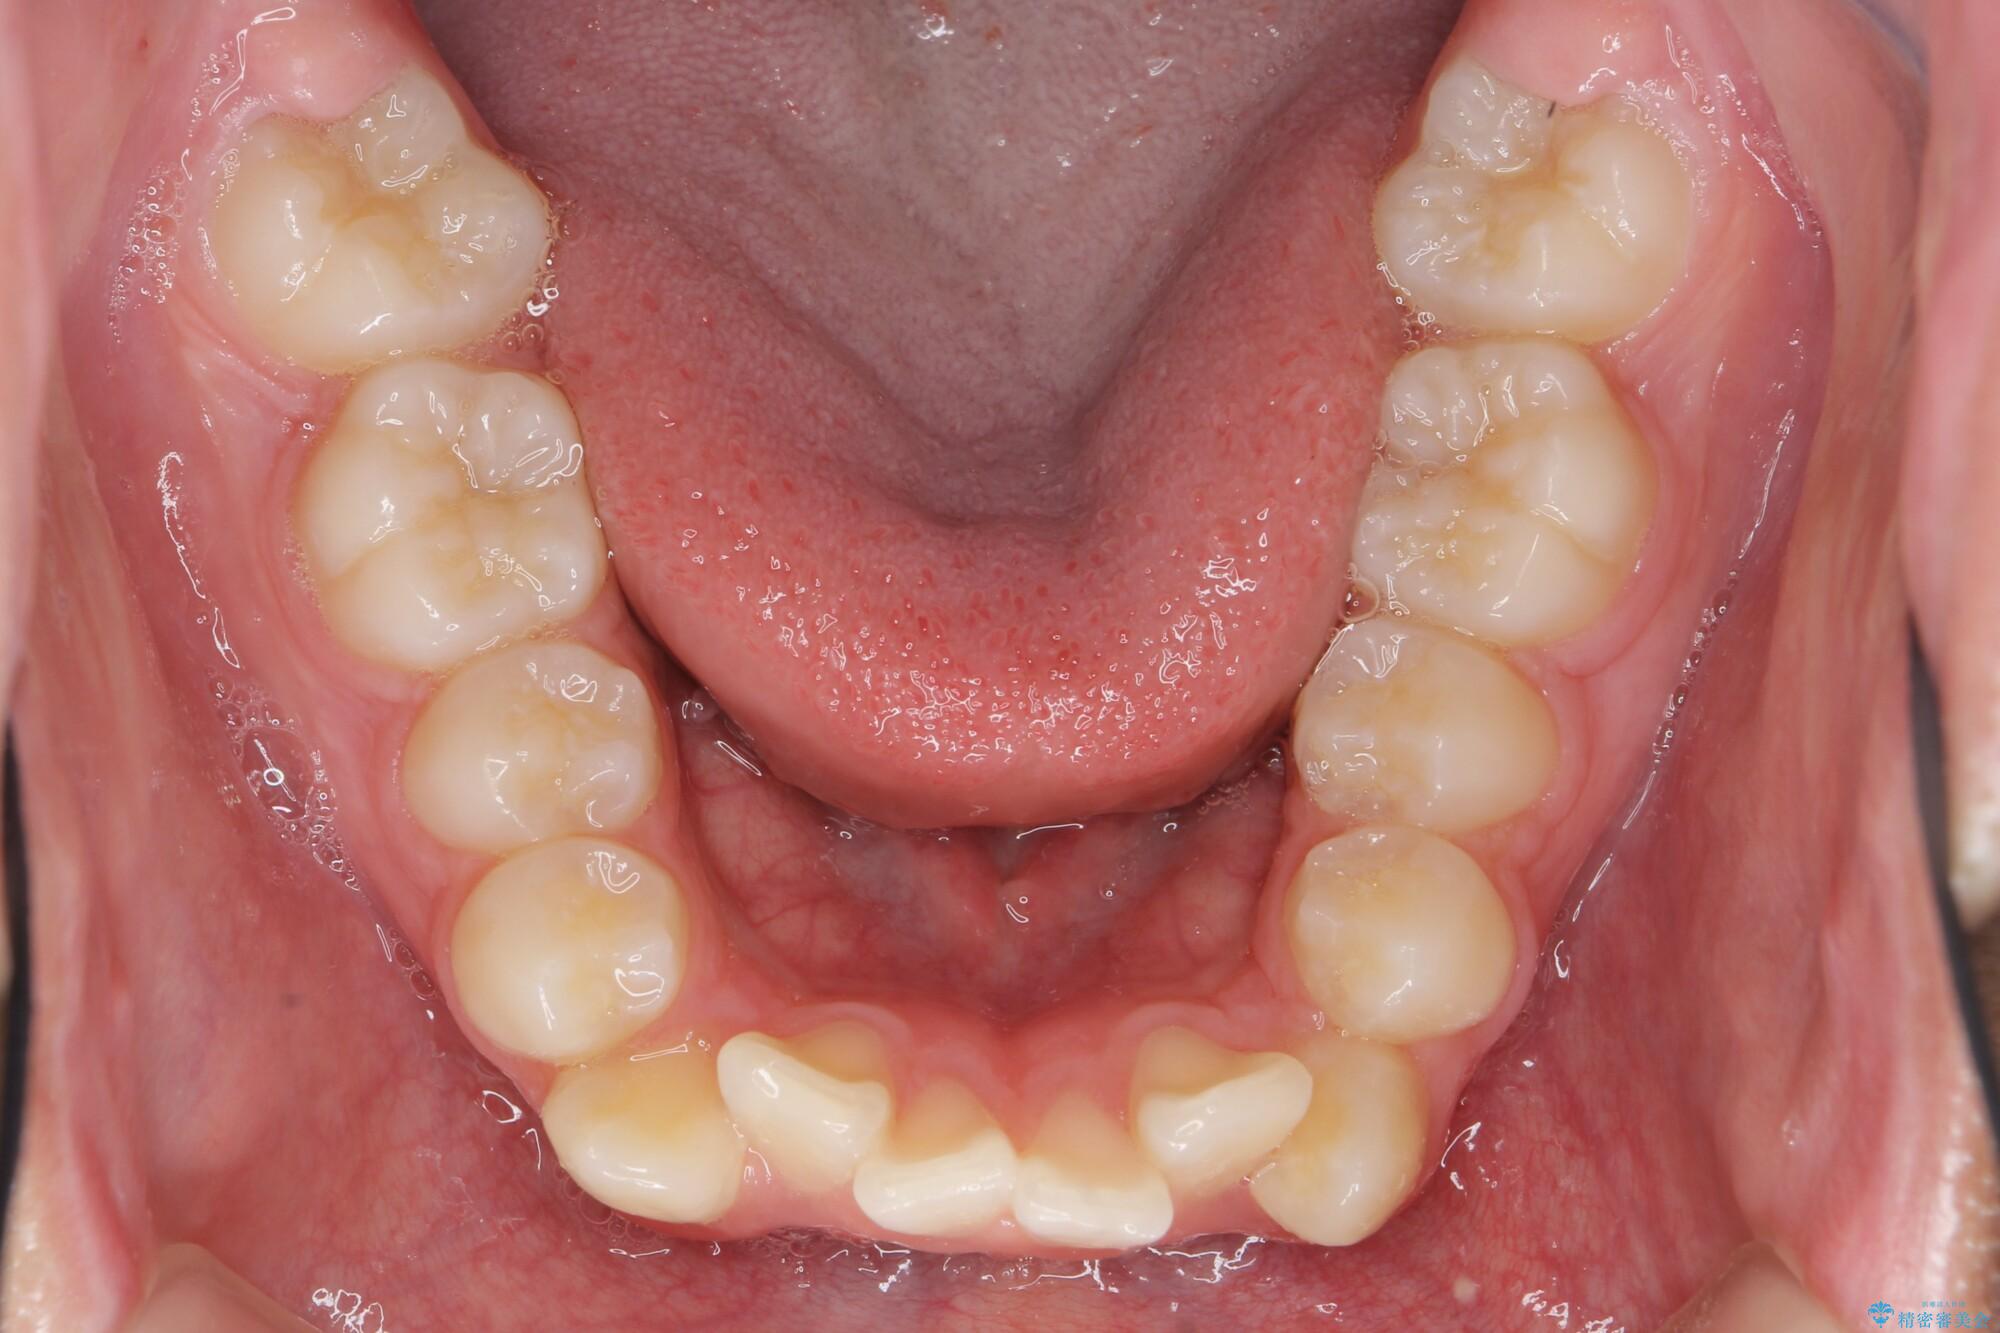

がちゃがちゃした前歯をきれいにしたい

- 前歯のがたつきが原因で歯ブラシしづらい、見た目を改善したい!と矯正治療を希望され来院されました。

スペースの不足が見られるため、小臼歯の4本抜歯を行いマルチブラケットを用いた矯正治療を計画します。

噛み締めが強く、治療に時間がかかりましたが矯正治療の仕上がりに満足いただくことができました。